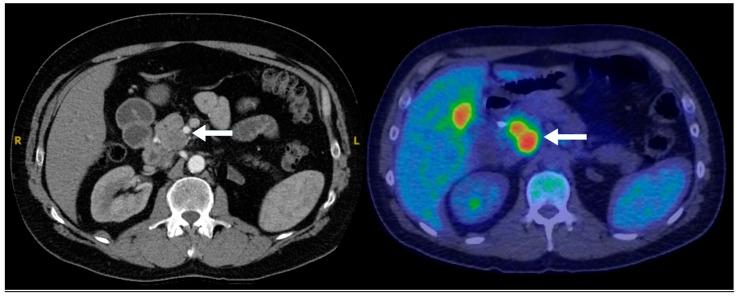

Pancreatic neuroendocrine neoplasms (PNENs) are rare but clinically significant tumors with variable radiological presentations that complicate diagnosis. While typical PNENs are well characterized, atypical features, such as cystic or hypoenhancing patterns, are less understood and can lead to diagnostic delays or misdiagnosis. This study aimed to evaluate atypical radiological presentations of PNENs, focusing on their impact on diagnostic pathways and differentiation from other pancreatic pathologies. A retrospective review was conducted of all PNEN cases diagnosed at a single tertiary center between 2010 and 2020. Cases with histopathological confirmation and available cross-sectional imaging were included. Radiological features were categorized as typical (solid and hyperenhancing) or atypical (cystic and hypoenhancing). Demographic, radiological, and pathological data were analyzed. Comparisons between typical and atypical PNENs were performed using descriptive and inferential statistics. Among 77 PNEN cases, 39 met the inclusion criteria. Atypical radiological presentations were identified in 46% of cases, including cystic (18%) and hypoenhancing (28%) lesions. Hypoenhancing PNENs were significantly more likely to present with advanced disease (54% vs. 14% in typical PNENs, = 0.016). In contrast, none of the cystic PNENs exhibited advanced disease. Atypical PNENs posed greater diagnostic challenges, with alternative diagnoses initially considered in 64% of hypoenhancing and 43% of cystic cases compared to 10% of typical PNENs ( = 0.0042). Atypical PNENs, particularly hypoenhancing lesions, present significant diagnostic challenges and are more likely to be associated with advanced disease. These findings highlight the need for improved recognition of atypical imaging patterns and more precise diagnostic strategies. However, the retrospective design and small cohort size limit the generalizability of our findings. Further multicenter studies are warranted to refine the imaging criteria and optimize the differentiation from other pancreatic neoplasms.

胰腺神经内分泌肿瘤(PNENs)虽罕见,但具有临床意义,其放射学表现多样,使诊断变得复杂。典型的PNENs特征明确,但非典型特征,如囊性或强化减弱模式,了解较少,可能导致诊断延迟或误诊。本研究旨在评估PNENs的非典型放射学表现,重点关注其对诊断途径的影响以及与其他胰腺病变的鉴别。对2010年至2020年在单个三级中心诊断的所有PNEN病例进行了回顾性研究。纳入有组织病理学证实且有横断面影像资料的病例。放射学特征分为典型(实性且强化明显)或非典型(囊性且强化减弱)。对人口统计学、放射学和病理学数据进行分析。使用描述性和推断性统计对典型和非典型PNENs进行比较。在77例PNEN病例中,39例符合纳入标准。46%的病例发现有非典型放射学表现,包括囊性病变(18%)和强化减弱病变(%)。强化减弱的PNENs出现晚期疾病的可能性显著更高(54%,而典型PNENs为14%,P = 0.016)。相比之下,囊性PNENs均未出现晚期疾病。非典型PNENs带来更大的诊断挑战,与典型PNENs的10%相比,64%的强化减弱病例和43%的囊性病例最初考虑了其他诊断(P = 0.0042)。非典型PNENs,尤其是强化减弱病变,带来显著的诊断挑战,且更可能与晚期疾病相关。这些发现凸显了提高对非典型影像模式的认识以及采用更精确诊断策略的必要性。然而,回顾性设计和小样本队列限制了我们研究结果的普遍性。有必要进行进一步的多中心研究以完善影像标准并优化与其他胰腺肿瘤的鉴别。